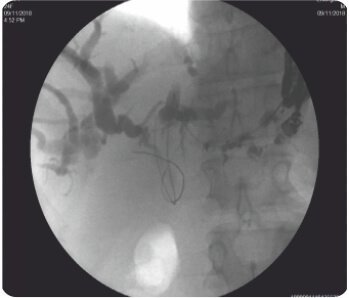

লিভারের দ্বিতীয় অংশে IHBRD এর EUS নির্দেশিত পাংচার পাকস্থলী থেকে করা হয়েছিল এবং কোলাঞ্জিওগ্রামের পরে, সিস্টোটোম ব্যবহার করে ট্র্যাক্টটি 10F পর্যন্ত ধারাবাহিকভাবে প্রসারিত করা হয়েছিল এবং পেট এবং লিভারের দ্বিতীয় অংশের সাথে সংযোগকারী একটি 60×10 মিমি সম্পূর্ণরূপে আবৃত বিলিয়ারি ধাতব স্টেন্ট স্থাপন করা হয়েছিল। ধাতব স্টেন্টের স্থানচ্যুতি রোধ করার জন্য ধাতব স্টেন্টের ভিতরে একটি 7F 7 সেমি ডাবল পিগটেল প্লাস্টিক স্টেন্ট স্থাপন করা হয়েছিল। কোনও পেরিপ্রোসিডেরাল জটিলতা ছিল না এবং বিলিরুবিনের স্বাভাবিকীকরণের পরে রোগীকে কেমোথেরাপি করা হয়েছিল। পদ্ধতির 3 মাস পরে ফলো-আপের সময়, রোগীর LFT স্বাভাবিক ছিল।

FCSEMS প্লেসম্যান

ভিতরে অ্যাপ্লাস্টিক স্টেন্ট সহ FCSEMS